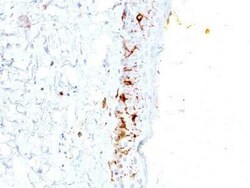

CD1a Antibody (C1A/711) - IHC-Prediluted, Novus Biologicals™

CD1a Monoclonal antibody specifically detects CD1a in Human samples. It is validated for Immunohistochemistry, Immunohistochemistry (Paraffin)

| Immunohistochemistry, Immunohistochemistry (Paraffin) | |

| Immunohistochemistry, Immunohistochemistry-Paraffin 0.5 - 1.0 μg/mL | |

| Recombinant full-length human CD1a protein (Uniprot: P06126) | |